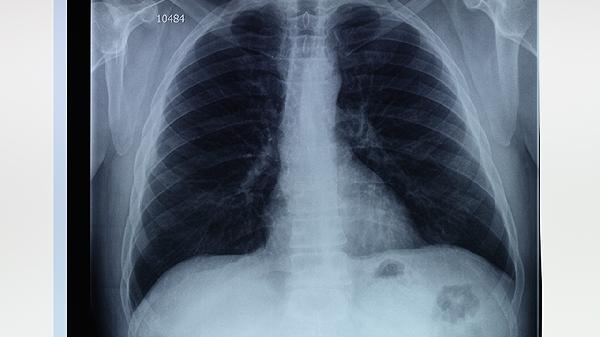

合理选择治疗方案后,患者还需注意日常调理,避免剧烈运动和突然改变环境气压,保持呼吸道湿润。特别是对于有过病史的患者,应定期复查胸部CT或X光片,监测肺大疱大小变化。